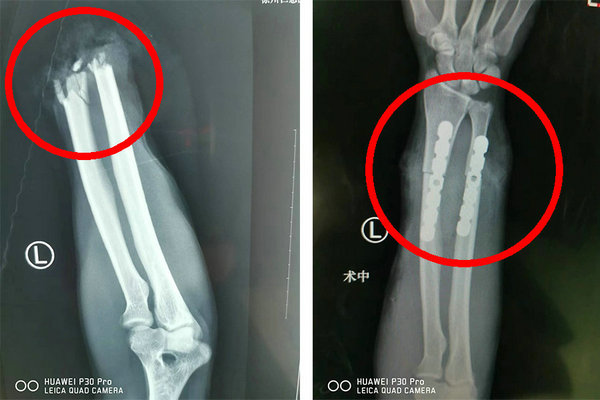

术中,医生先仔细清除尺桡骨断端周围游离骨碎片及血凝块,钢板固定骨折断端,吻合动静脉先让肢体通血,然后一一修复断裂的肌腱、肌肉、神经、韧带……一切都在紧张而有序的进行着。